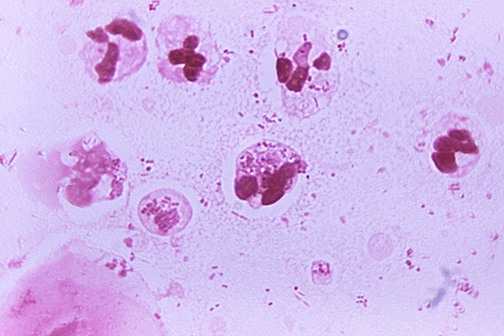

LSU Health New Orleans Develops New Human Cell Line to Study Blinding Eye Disorders

Under the direction of Boyd Professor Nicolas Bazan, MD, PhD, scientists at LSU Health New Orleans Neuroscience Center of Excellence have developed a new, experimental human cell line from retinal pigment epithelial cells. Called ABC, these cells so closely resemble and retain the properties of native retinal pigment epithelial (RPE) cells, the research team has shown that they are a reliable cell system to study retinal degenerative diseases. More

LSU Health Contributes to Research Suggesting Late-Onset Retinal Degeneration Mechanism & Potential Rx

A study led by the National Eye Institute (NEI) that included five researchers from the Bazan Lab at the LSU Health New Orleans Neuroscience Center of Excellence has discovered how late-onset retinal degeneration can develop and a surprising potential therapeutic -- metformin. The results are published online in Communications Biology, a Nature journal. More